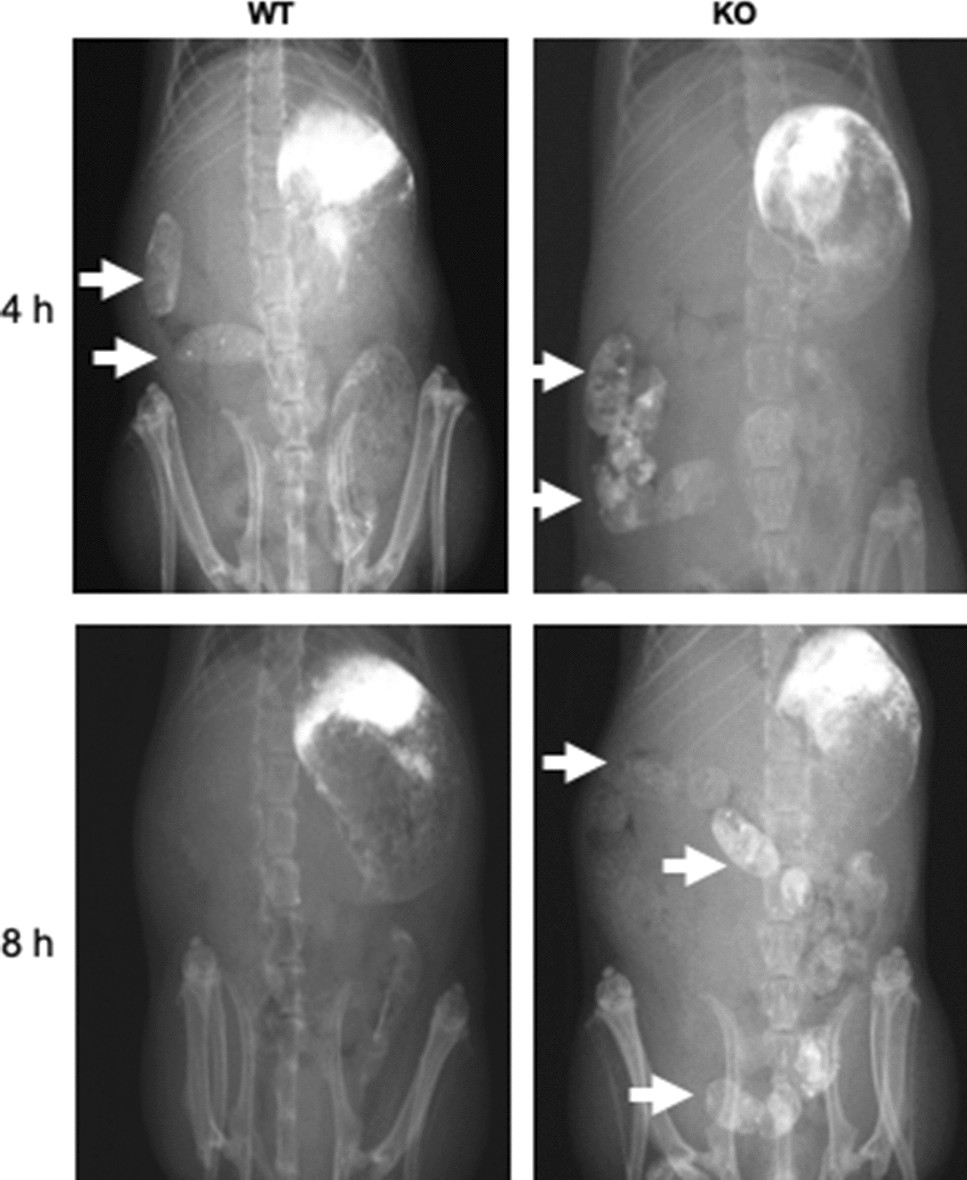

Figure 3

Intestinal transit time of the BALB/c Kif26a-KO mice. Barium sulfate was administered orally and radiographs obtained after 4 and 8 h. Barium is observed in the large intestine of the WT (n = 4, 20-week-old female), and KO (n = 4, 20-week-old female) mice at 4 h. After 8 h, barium sulfate remains in the large intestine (arrows) of the KO mice but has been excreted from the large intestine in the WT mice. Areas in the upper left part of each radiograph are associated with barium sulfate that remained attached to the stomach lining.